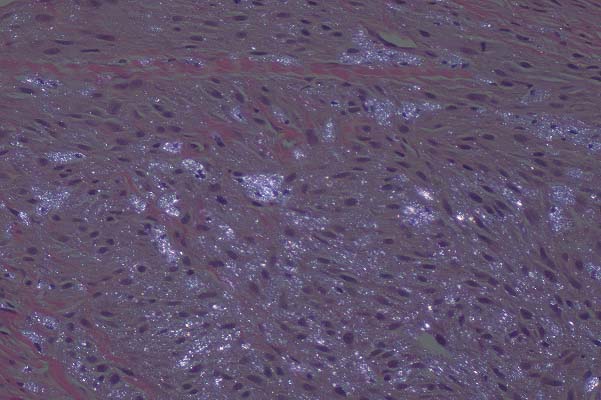

- The most characteristic lesions associated with cutaneous

chytridiomycete infection are hyperkeratosis and acanthosis.

Focal epidermal cell hypertrophy and/or degeneration are less

common. Inflammation is rare and, when it does occur, is usually

mild. Typically, low to moderate numbers of chytridiomycetes

are located in the superficial epidermis, primarily the keratinized

layers. In histologic sections, three stages of the organisms

are primarily seen: a uninucleated form, a multinucleated stage

containing internal septa, and a cyst-like form (zoosporangium)

containing multiple flagellated spores (zoospores). Each spore

has a single posterior flagellum that is very difficult to detect

in histologic sections.

40x

obj

- Case 29-4. Skin. Multiple developmental stages of

fungal thalli and zoosporangia are present within the epidermis

and subepidermal glands.